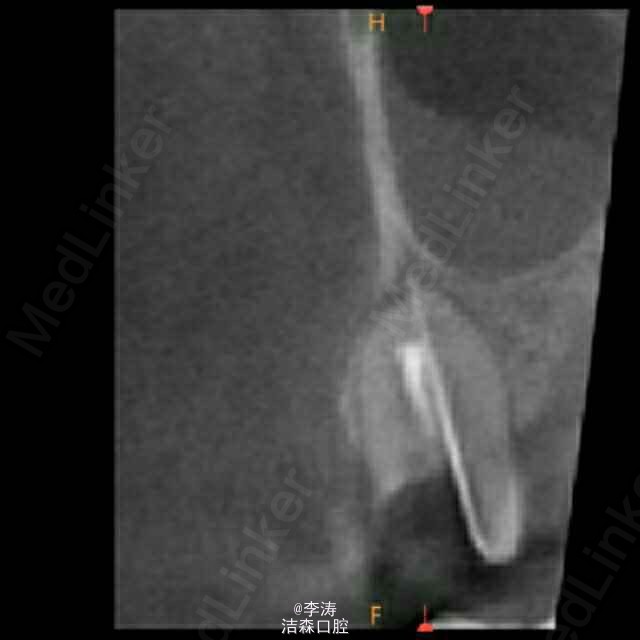

过台阶根管再治疗一例

15牙因根管治疗后牙折裂,行根管再治疗

根管预备形成台阶1例

年轻恒牙;根管再治疗;消除台阶